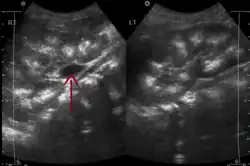

Rozpoznanie stawiane bywa przypadkowo na podstawie przeglądowego zdjęcia rentgenowskiego jamy brzusznej, ujawniającego drobne zwapnienia w nerce (nefrokalcynoza) albo przy próbie diagnostyki krwiomoczu, kamicy lub zakażeń układu moczowego. Badaniem obrazowym o największej czułości jest urografia[2].